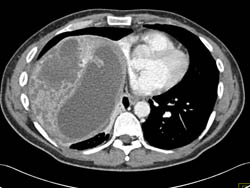

CTA Liver That Is Infiltrated By Tumor and Chemoembolization for Hepatoma